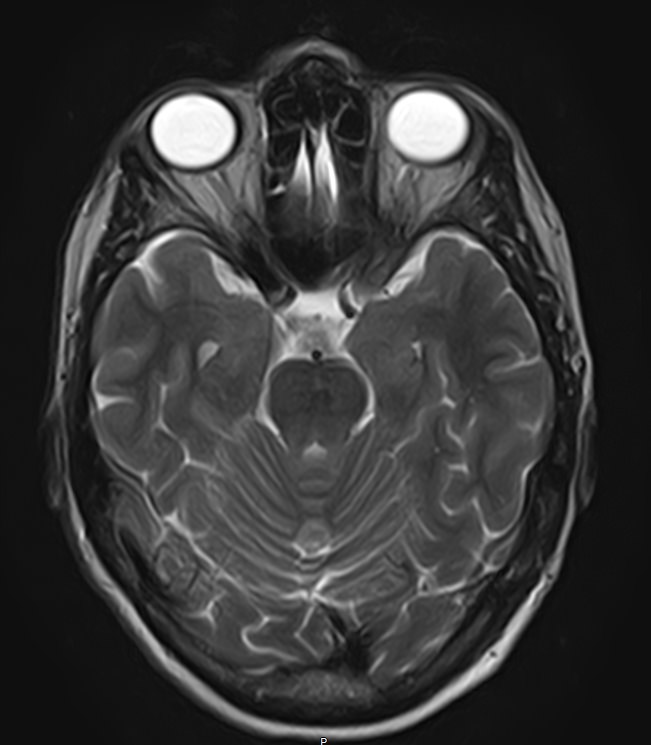

Стандартная МРТ головного мозга дает важную информацию о состоянии и структуре мозговой ткани для выявления большого числа заболеваний, в том числе опухолевых образований, демиелинизирующих заболеваний, воспалительных процессов головного мозга и мозговых оболочек. Стандартную МРТ головного мозга дополняет МР-ангиография, которая отображает состояние артериальной системы кровоснабжения головного мозга. МР-венография головного мозга позволяет детально изучить особенности анатомического и функциональной состояния венозного русла головного мозга.

Компьютерная программа обрабатывает данные, полученные при сканировании, и формирует объемные изображения как самого мозга, так и сосудистой системы в отдельности без прилегающих тканей. Обе методики применяются одновременно и взаимодополняют друг друга, давая полную диагностическую картину.